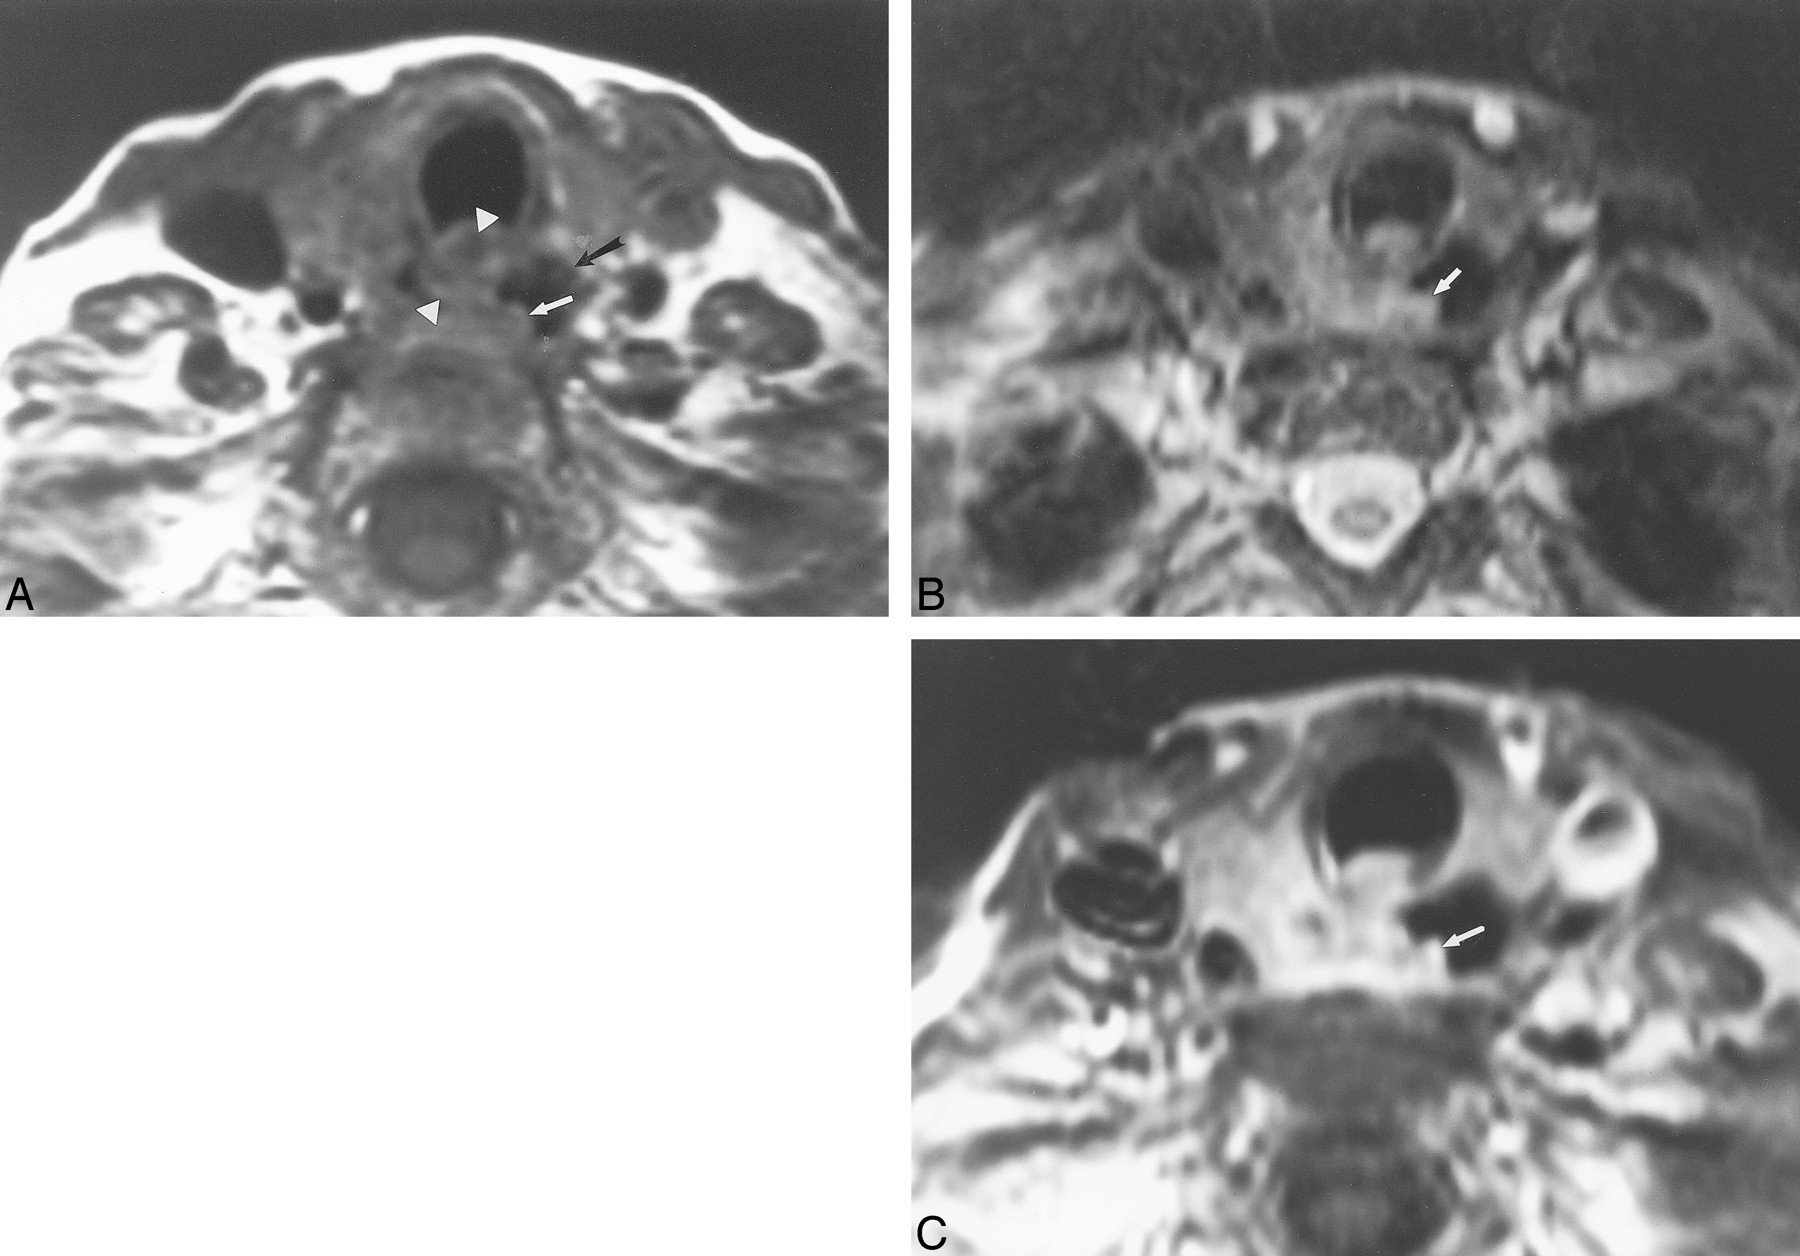

This 72-year-old woman had follicular carcinoma of the left lobe of the thyroid. This case represents a false-positive interpretation of esophageal invasion. There was no evidence of esophageal invasion by surgical or pathologic evaluation.

A, Axial T1-weighted image (700/17) shows effacement of the fat plane between the esophagus and the left thyroid (arrow).

B, Axial T2-weighted image (3000/78) shows focal increased signal within the esophageal wall adjacent to the thyroid mass (arrowheads) compared with the normal right lateral wall of the esophagus (arrow).